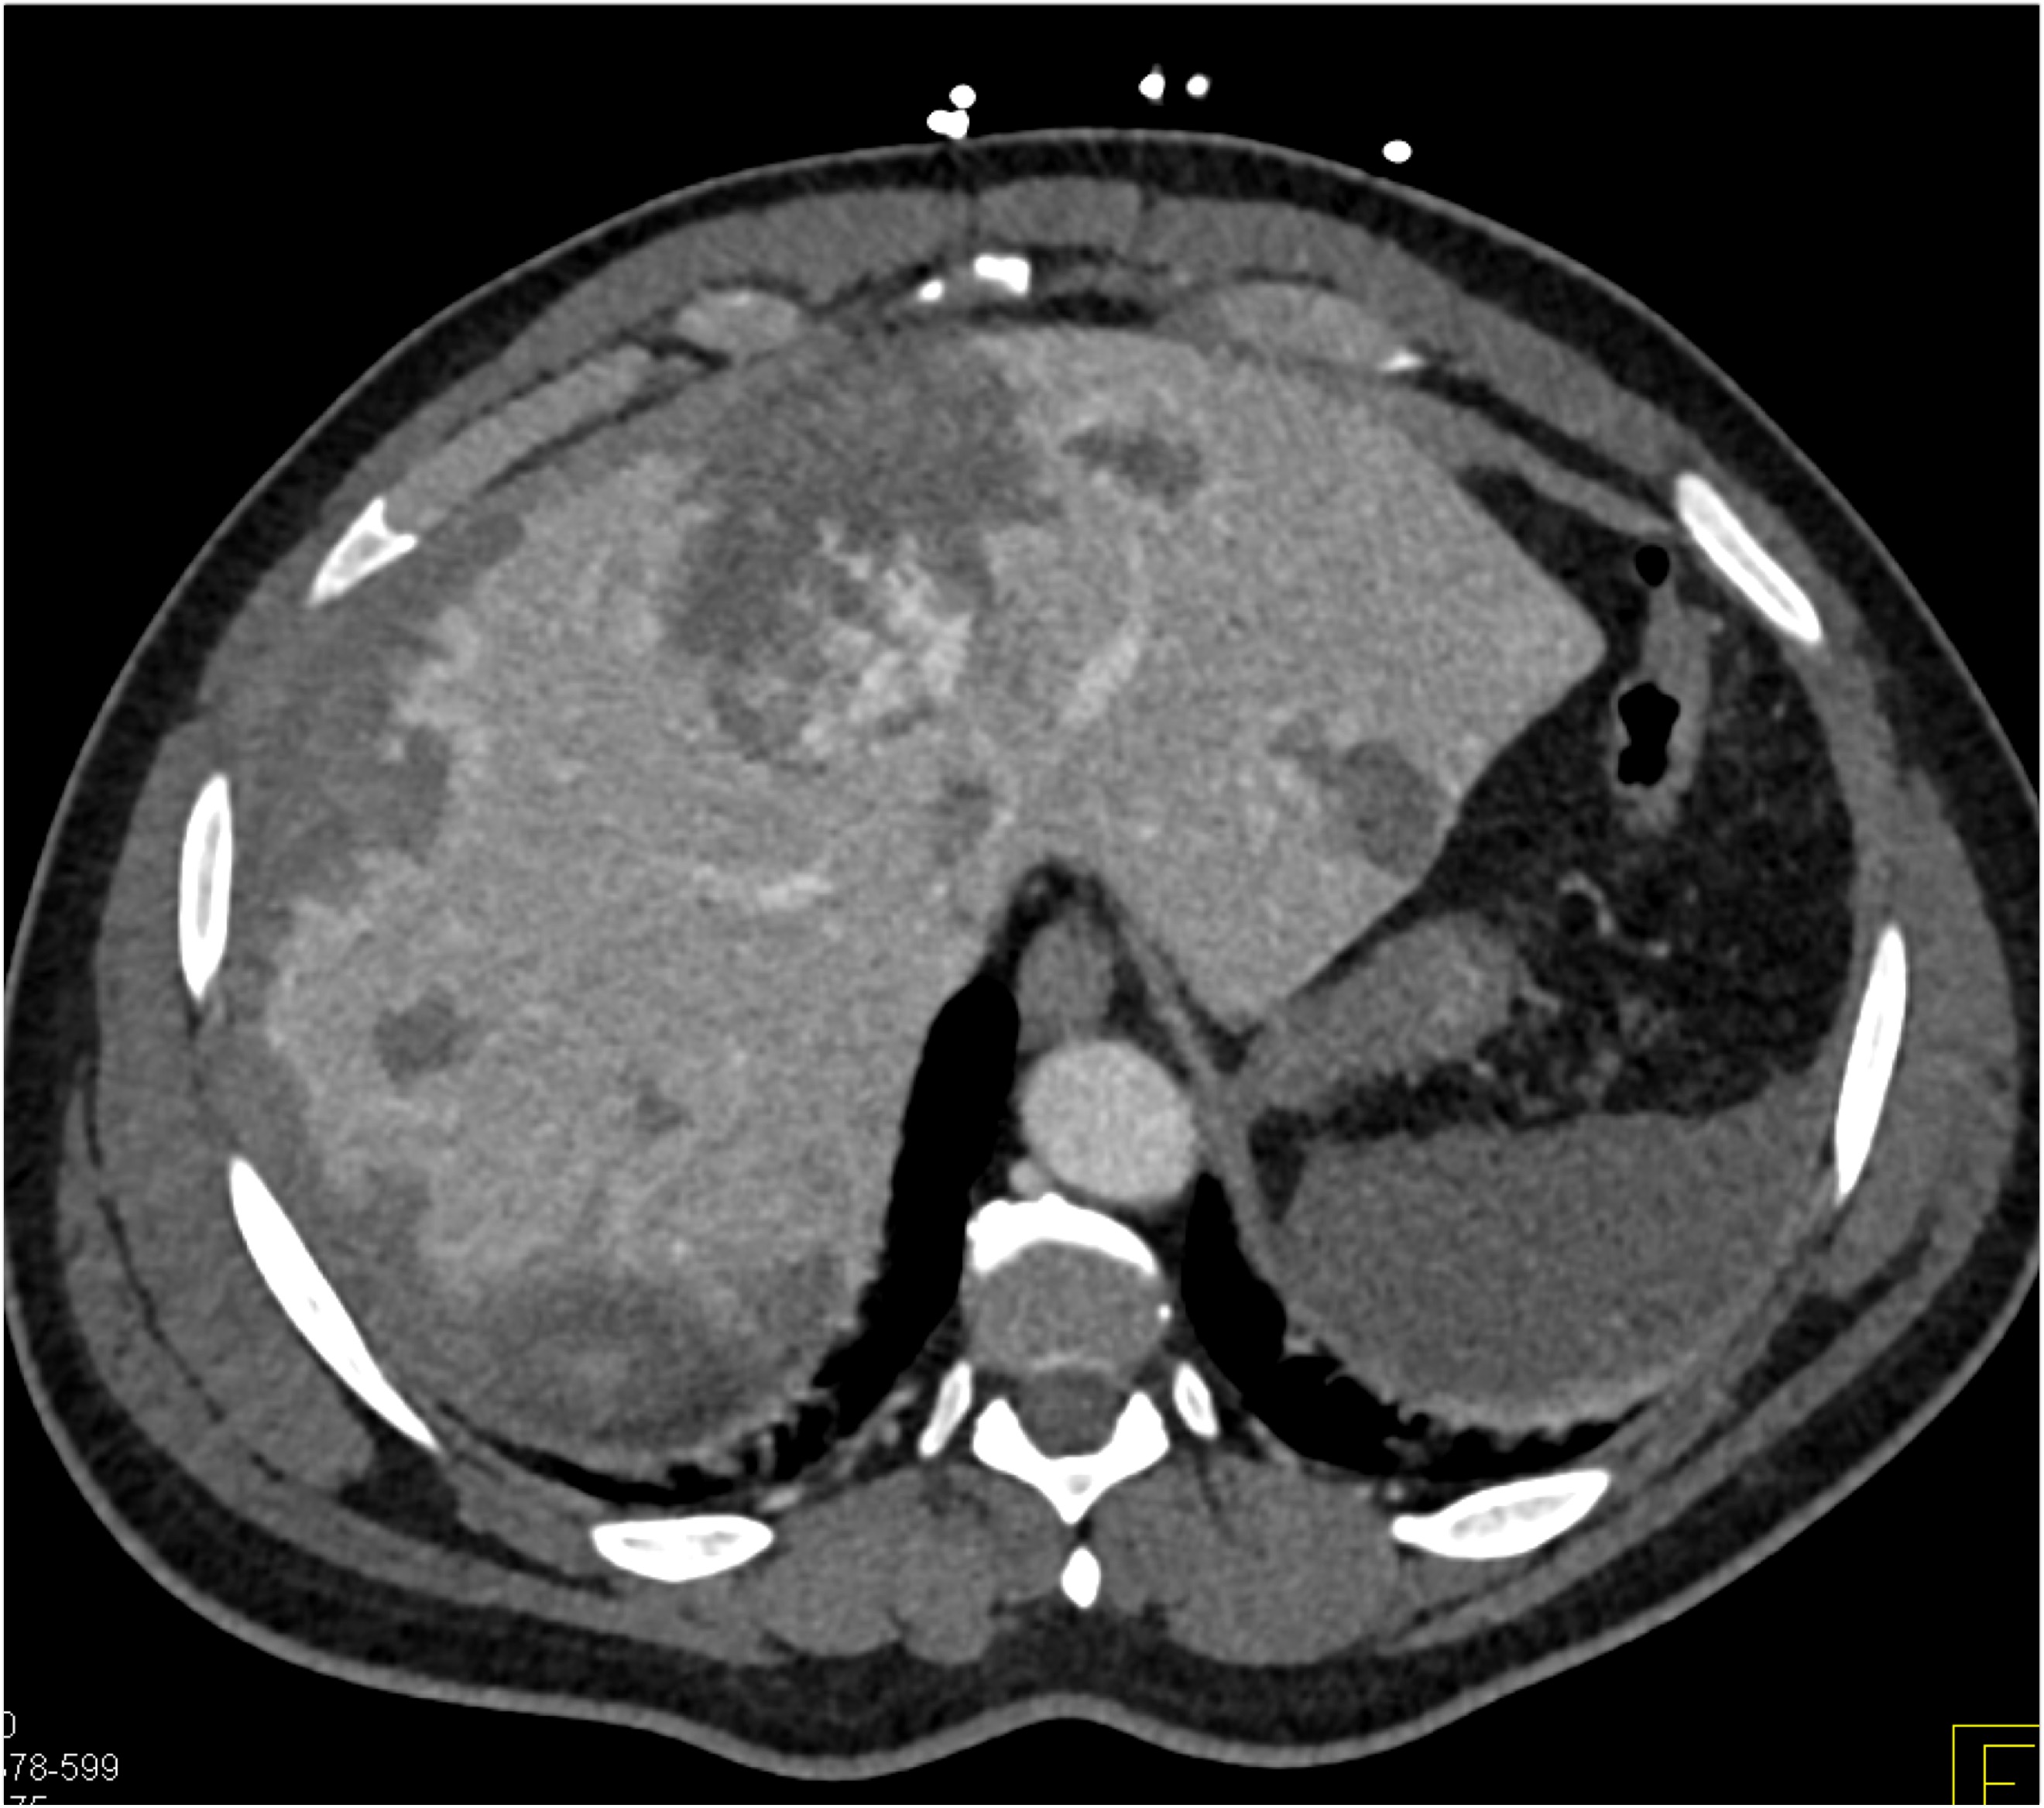

8) In this patient with RUQ pain and no history of trauma the best diagnosis is?

multiple hemangiomas

focal nodular hyperplasia

hepatic adenomas

angiosarcoma of the liver